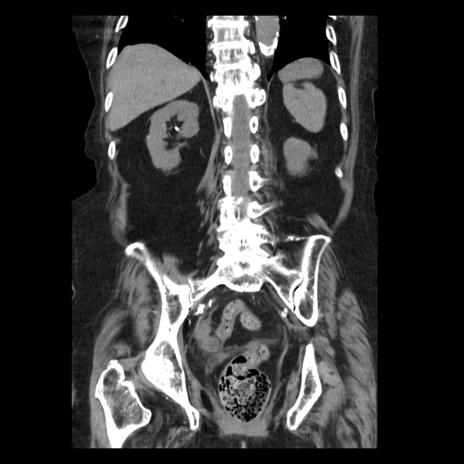

横断像